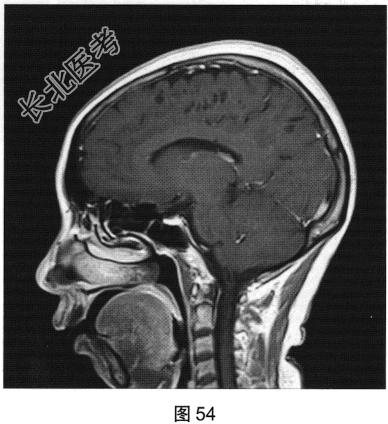

- [材料题] 患者女性,56岁,诉头痛、头晕多年,要求行颅脑MRI检查。查体:神志清楚,问答切题,查体合作。双眼睑无水肿、下垂及闭合不全,双侧瞳孔直径约3.0mm,直接、间接反射均灵敏。双眼视力视野粗侧无异常。发音清晰无嘶哑。耸肩及转头力量对称。四肢活动灵活,肌力、肌张力正常,深浅感觉基本正常;病理征阴性。患者行颅脑MRI检查,如图41~图44所示。

- 多项选择题2.[提示]患者行FLAIR、DWI及增强扫描,见图45~图54。该患者MRI影像的主要阳性表现有( )

C、双侧放射冠及半卵圆中心多发条状、圆形及卵圆形异常信号灶

E、病灶呈长T1、长T2信号,FLAIR为低信号,DWI为低信号,ADC为高信号